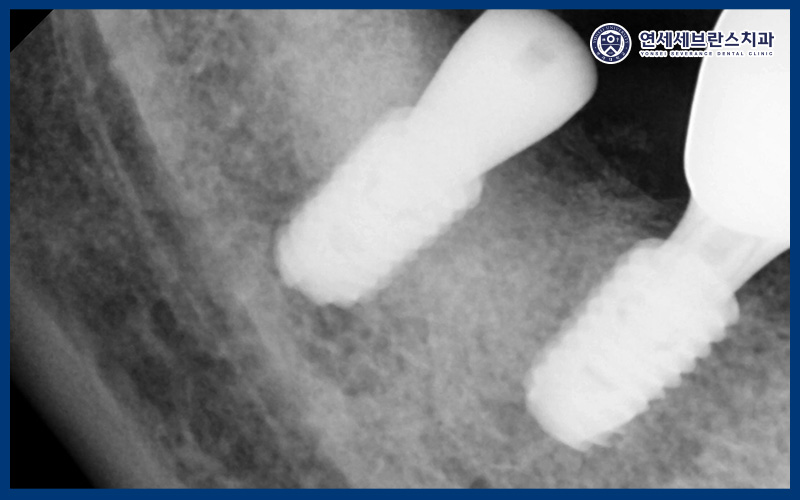

먼저 위쪽 치아들을 발치한 뒤,

상악동 측방 거상술을 통해

상악동 공간을 확보하고

부족한 뼈를 보강하였습니다.

이후 임플란트가 안정적으로

고정될 수 있는 환경을 조성한 다음,

계획에 따라 임플란트를 식립하였습니다.

임플란트는 식립 후 약 한 달 동안의

초기 고정이 매우 중요한 만큼,

한 달 뒤 내원하여 치유 과정이

안정적으로 진행되고 있는지

확인하였습니다.

내원 시 염증 소견 없이

주변 조직이 잘 회복되고 있었으며,

임플란트 역시 흔들림 없이

양호한 상태를 유지하고 있음을

확인할 수 있었습니다.